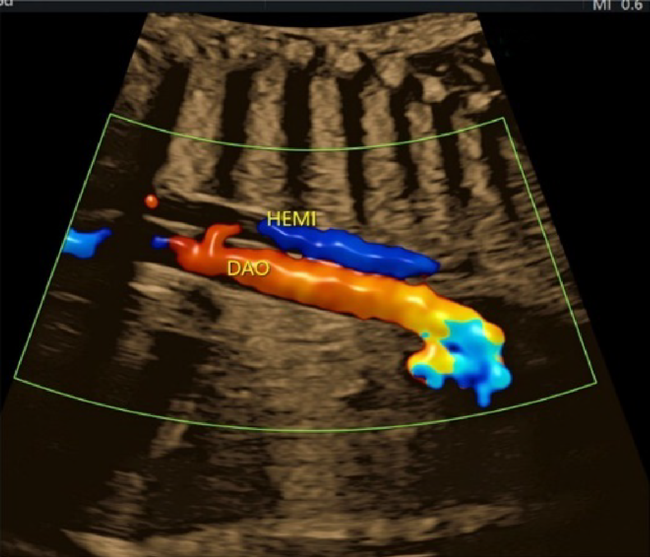

(6) Sagittal Cross-Sections of the Aortic Arch and the Ductal Arch

The aortic arch originates from the left ventricle and forms a convex shape with three branches in the cranial direction (Fig. 13). The ductal arch originates from the right ventricle and is of a similar diameter to the main pulmonary arterial trunk, the ductus arteriosus, and the descending aorta (Fig. 14). These two arches are observed in normal and healthy fetuses.

Coarctation of the aorta is difficult to diagnose in the absence of other structural abnormalities of the heart. It is to be suspected when; the aortic isthmus diameter Z score ≤−2.0, the ratio of the diameter of the ductus arteriosus to that of the aortic isthmus ≥1.5, continuous or retrograde blood flow present in the aortic isthmus, a posterior shelf obvious at the aortic isthmus, or structures of the left heart small.57)